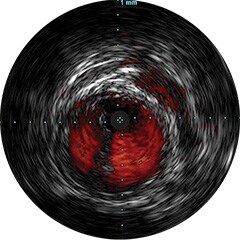

Einführung der völlig neue Anwendungsplattform IntraSight von Philips – Zusammenspiel von Bildverarbeitung, Physiologie, Koregistrierung und Software für eine optimale Patientenversorgung. IntraSight bietet eine umfassende Palette klinisch bewährter Modalitäten wie iFR/FFR, IVUS und Koregistrierung* für einfachere komplexe Interventionen, schnellere Routineverfahren und eine verbesserte Patientenversorgung.

IntraSight ist auf Basis einer intelligenten, anwendungsbasierten Plattform konzipiert, die sich bei neuen verfügbaren Anwendungen und Modalitäten an die sich ändernden Anforderungen Ihres Labors anpassen lässt – und das ohne neue Hardware erwerben zu müssen. Nur IntraSight von Philips bietet Ihnen erstklassige Bildverarbeitungs- und Physiologie-Tools mit iFR, iFR-Koregistrierung*, FFR, IVUS, IVUS-Koregistrierung* und Angio+*. Dank seiner modularen Architektur bleibt IntraSight über die neuesten Entwicklungen und wichtigen Sicherheitsupdates auf dem Laufenden.

Digitale IVUS- Bildverarbeitung